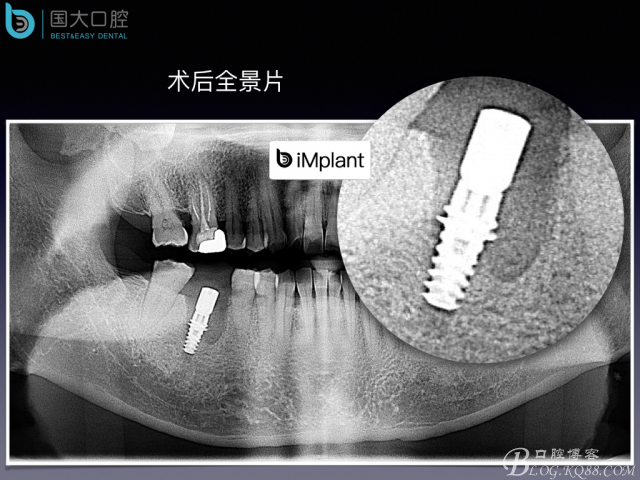

頰側(cè)骨壁嚴(yán)重缺失,應(yīng)該如何設(shè)計種植位點?

來源于國大口腔 邵現(xiàn)紅醫(yī)生發(fā)表的博文